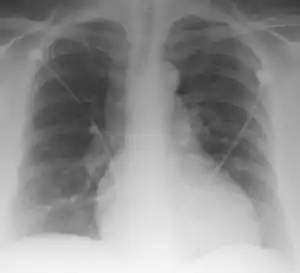

Palla's sign is a clinical sign in which an enlarged right descending pulmonary artery is seen on the chest x-ray in patients with pulmonary embolism. It is of low sensitivity, and its specificity is not known. It exhibits as a "sausage" appearance on X-ray. [1] It is named after italian radiologist Antonio Palla. In 1983, he published his observations that close to 25% of patients with pulmonary embolism had a chest x-ray sign of enlarged right descending pulmonary artery.[2][3]

| Palla Sign and Westermark Sign | |